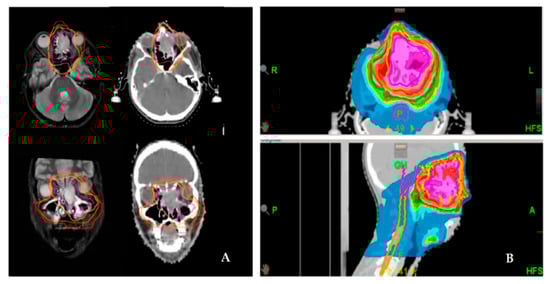

For definitive RT, gross tumor volume (GTV) was defined on planning MRI and contrast-enhanced CT. For adjuvant RT planning, the preoperative and the postoperative images were also coregistered to the planning CT scan. Over the years, two different boost concepts were applied: sequential boost concept (SEQ) and simultaneous integrated boost concept (SIB). For adjuvant treatment, after delineation of the pre-surgery GTV, an isotropic margin of 5 mm for SIB 1 and 10 mm for SIB 2 and 10 mm for SQB by the TPS was deemed as the clinical target volume (CTV1 or SIB1, respectively) was generated. Manual correction on each slice fitted the CTV1/SIB1 to anatomical borders (e.g., bone). For definitive treatment in cases of SIB planning, the SIB2 volume was created by another 5 mm margin around SIB1 (Figure 1). For the planning target volume (PTV) for both radiation settings, a further 5–10 mm and a set-up error of max. 3 mm was generated and manually corrected on each slice. The cervical lymph node levels I-III and retropharyngeal nodes were irradiated only in cases of histologically positive cervical lymph nodes or with macroscopic evidence in definitive situations.

Figure 1. Delineation and dose distribution by helical tomotherapy of a left-sided paranasal carcinoma with orbital involvement. Definitive radiation treatment was performed using a SIB concept on Hi-Art tomotherapy (A). Delineation of the target volume on both CT and MRI scans (magenta: GTV; yellow: SIB-1; orange: SIB-2; red: PTV). (B). Dose distribution as a color wash.